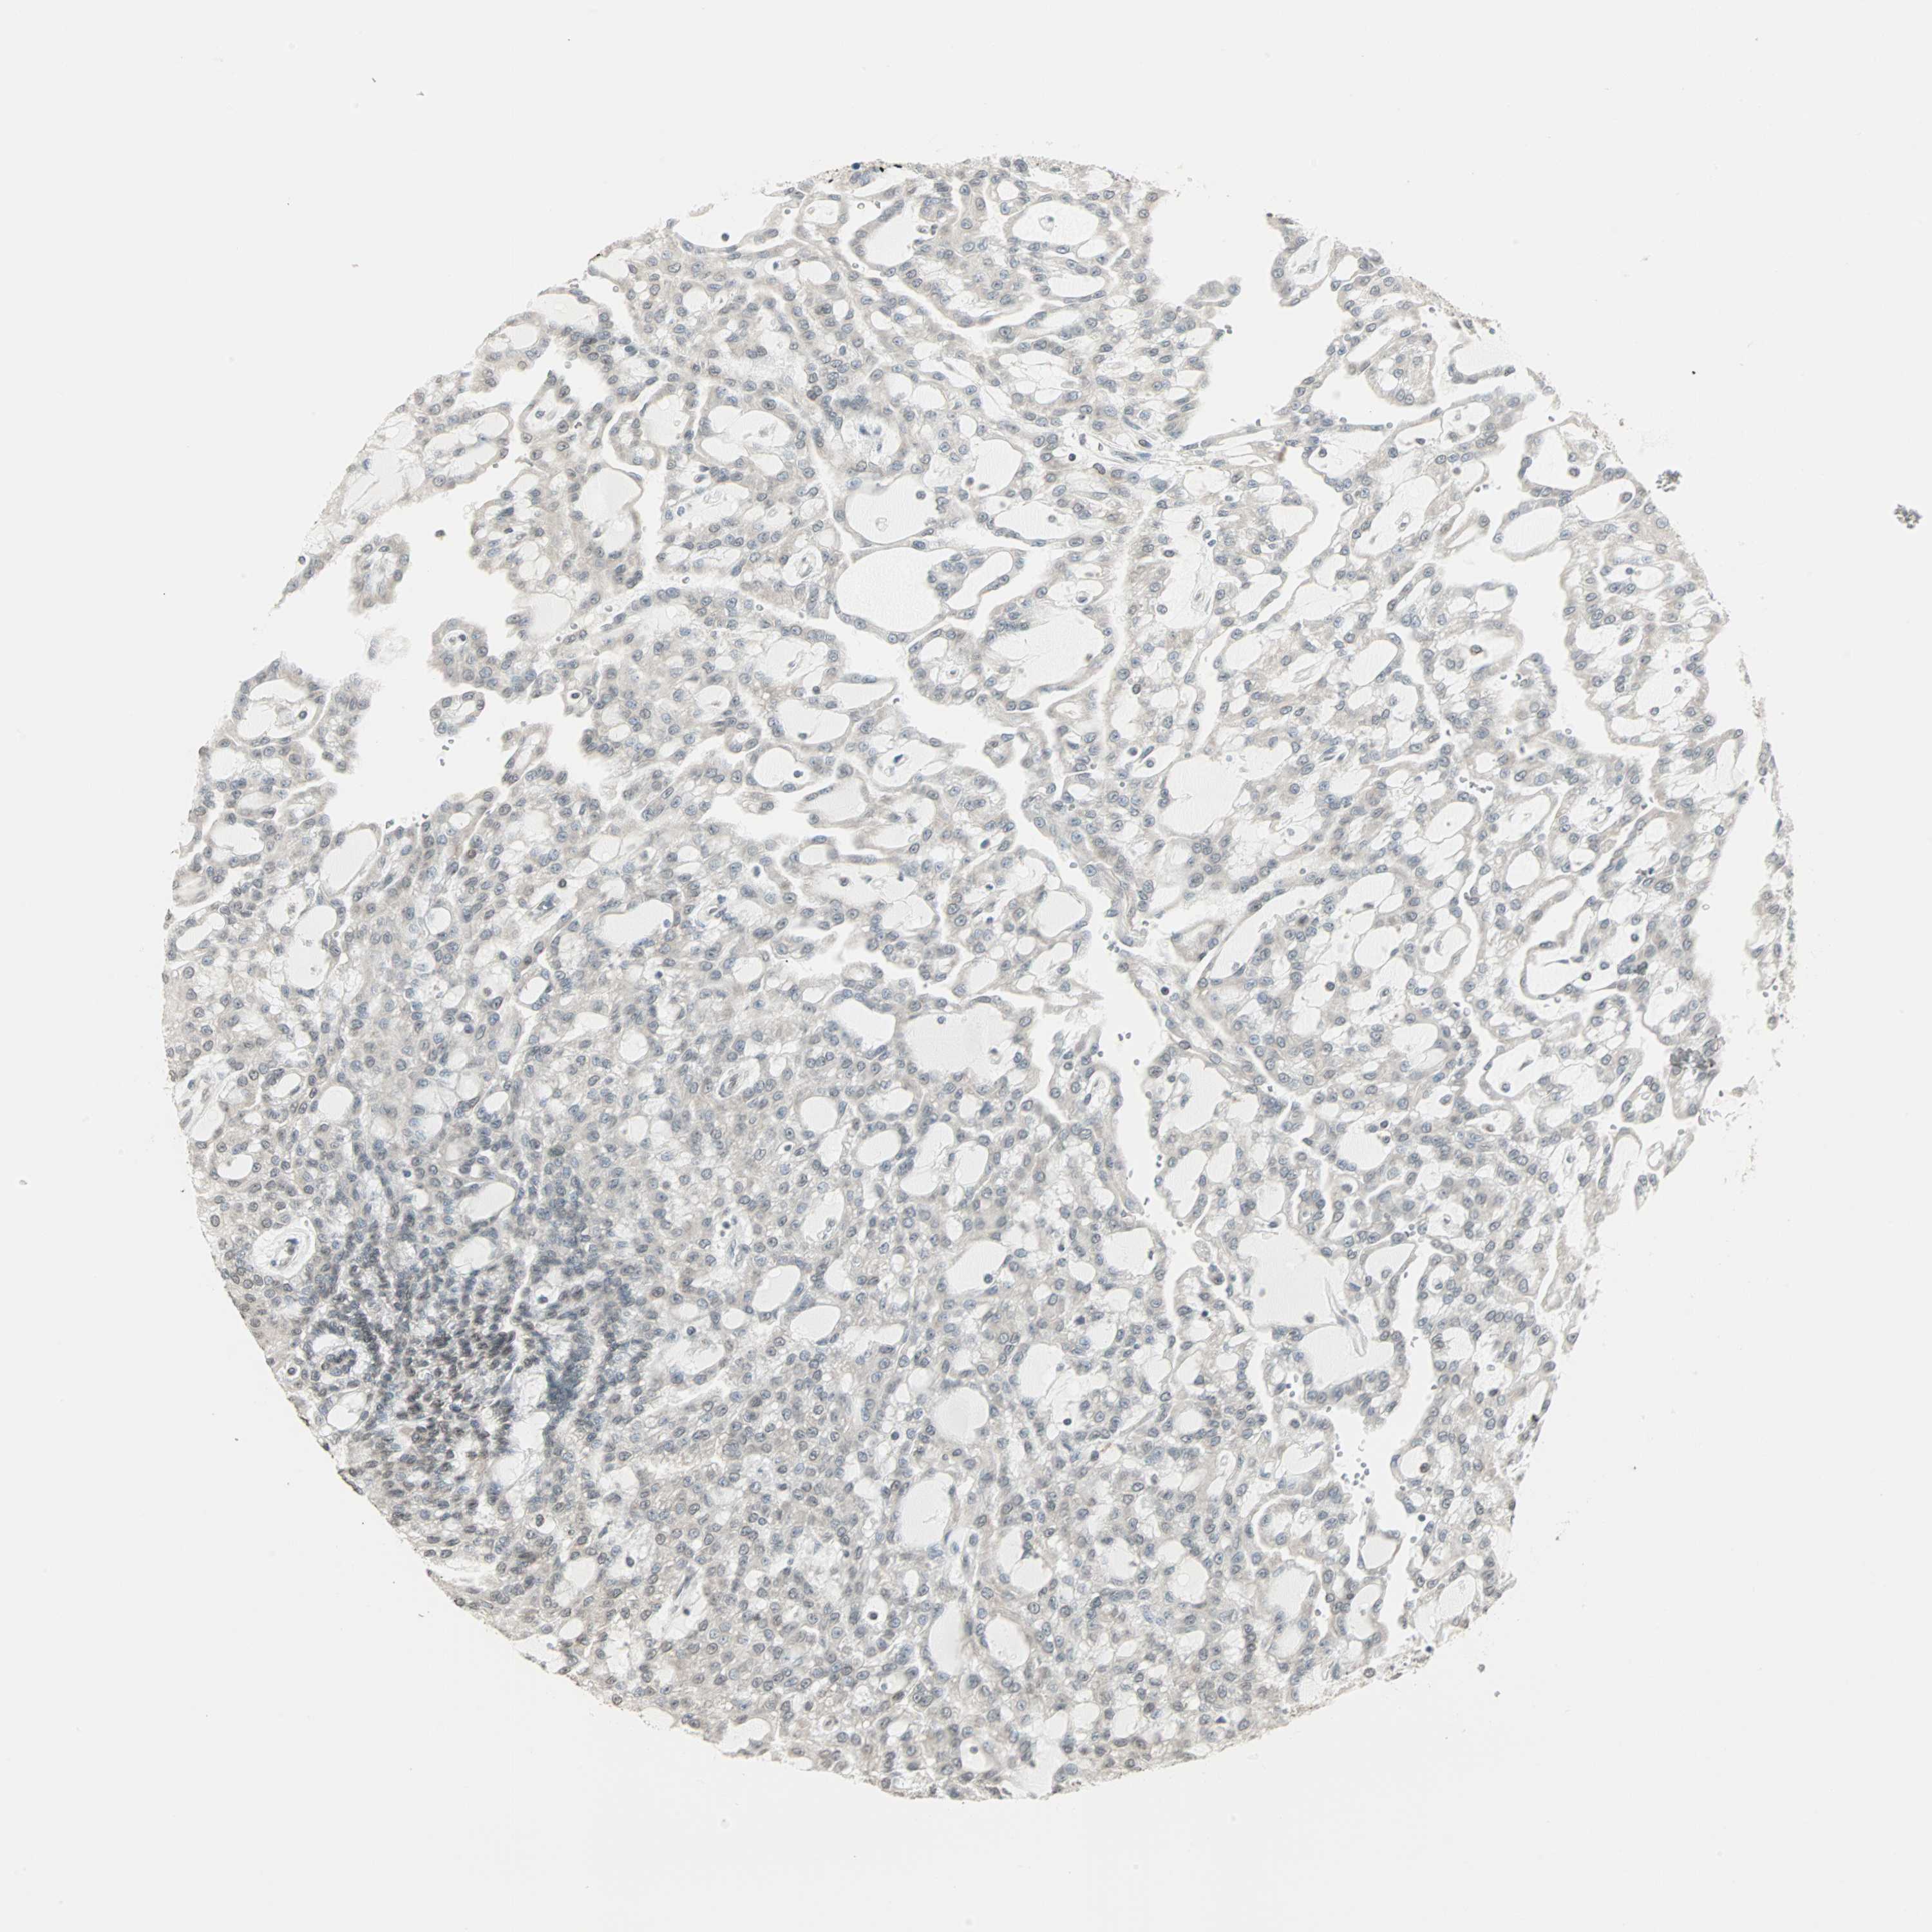

CANCER RENAL CANCER Show tissue menu

KICH TCGA KIRC TCGA KIRC VALIDATION KIRP TCGA PROTEIN RCC CPTAC PROTEIN EXPRESSION

CBLC is not prognostic in Kidney Renal Clear Cell Carcinoma (TCGA)

Average pTPM 1.2

Number of samples 521